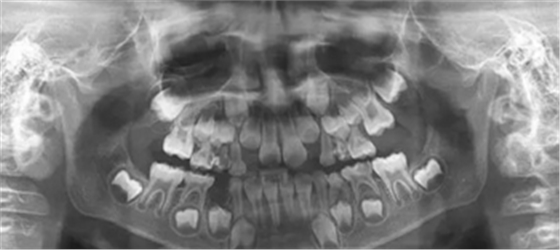

1、 患者 男 7歲 右下乳IV因齲早失

3、曲面斷層片 示恒牙萌出間隙不足